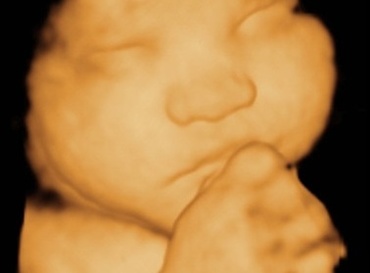

Saptamana 30 de sarcina

Incepe luna a VII-a. Nerabdarea incepe sa-si spuna cuvantul.